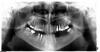

Enigma Опубликовано 1 июня, 2009 Поделиться Опубликовано 1 июня, 2009 (изменено) Вверху слева 4-ка потемнела после сделанной 10 лет назад резекции, но никогда не беспокоила за все это время. Решила закрыть коронкой. Каналы перелечили, поставили вкладку и временную коронку. На третий день после установки вкладки появился небольшой флюс. Была сделана вторая резекция на этот зуб, и заложен костный материал. Через два месяца после резекции снова появился флюс очень плотный на ощупь. Десна и зуб при нажатии и постукивании не болят. Хирург сказал, что это - костная мозоль, и рекомендовал наблюдаться. Я опасаюсь, что может быть раскол зуба вкладкой, т.к. она достаточна массивна. Неужели, я близка к истине, и зуб придется удалять? Все мучения и потраченные деньги напрасны? Внизу под 4-кой слева зубы-антогонисты 4-ка, 5-ка, 6-ка и 7-ка отсутствуют. Ношу съемник. Нагрузка на левую сторону при жевании значительно меньше, чем на правую. ОПТГ через месяц после резекции. Изменено 1 июня, 2009 пользователем Enigma Ссылка на комментарий

Doc Опубликовано 1 июня, 2009 Поделиться Опубликовано 1 июня, 2009 По этому снимку что-то хорошее сказать про Ваш зуб сложно. Если хотите убедиться на 100 процентов (или хотя бы на 95), что зубу хана, то сделайте КТ (компьютерная томография). Ссылка на комментарий

Андрей Опубликовано 1 июня, 2009 Поделиться Опубликовано 1 июня, 2009 Вверху слева 4-ка потемнела после сделанной 10 лет назад резекции, но никогда не беспокоила за все это время. Решила закрыть коронкой. Каналы перелечили, поставили вкладку и временную коронку. На третий день после установки вкладки появился небольшой флюс. Была сделана вторая резекция на этот зуб, и заложен костный материал. Через два месяца после резекции снова появился флюс очень плотный на ощупь. Десна и зуб при нажатии и постукивании не болят. Хирург сказал, что это - костная мозоль, и рекомендовал наблюдаться. Я опасаюсь, что может быть раскол зуба вкладкой, т.к. она достаточна массивна. Неужели, я близка к истине, и зуб придется удалять? Все мучения и потраченные деньги напрасны? Внизу под 4-кой слева зубы-антогонисты 4-ка, 5-ка, 6-ка и 7-ка отсутствуют. Ношу съемник. Нагрузка на левую сторону при жевании значительно меньше, чем на правую. ОПТГ через месяц после резекции.Снимок не четкий, ничего не видно. Но чую, что дело идет к удалению. Ссылка на комментарий

Enigma Опубликовано 1 июня, 2009 Автор Поделиться Опубликовано 1 июня, 2009 Изменила размер файла. Может, сейчас снимок будет четче. А некрупновата ли вкладка на 4-ке? От чего зависит размер вкладки? Какие вкладки по форме и по размеру должны быть в норме? Не кажется лм вам, господа, что зубу еще бы жить да жить, если бы не косяк ортопеда? Ссылка на комментарий

Bier Опубликовано 2 июня, 2009 Поделиться Опубликовано 2 июня, 2009 24, 47 зубы на выход. Ссылка на комментарий